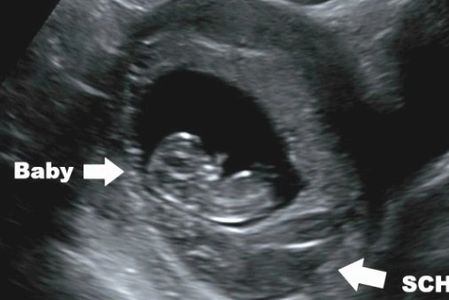

Bleeding is common. It almost always arises from the placenta or placental margin (occasionally from the cervix- Cervix infection and irritation can cause bleeding at any time in pregnancy). Placental bleeding may or may not form a subchorionic hemorrhage (SCH). Subchorionic hemorrhage may be very small and hard to visualize, or very large- even larger than the pregnancy. Older blood appears dark by ultrasound, more recent bleeding appears echogenic (brighter). What causes placental bleeding and subchorionic hemorrhage? Remember the placenta (which arises from baby) is attached to the uterus (you). Think of it as a special kind of glue. We want the glue to work well throughout pregnancy, but we want it to become unglued so the placenta can also deliver soon after birth of the baby. In the mean time, the uterus is growing, the placenta is growing, and the uterus has lots of contractions to help it grow. So...we are asking a lot from that special glue, and it's not surprising it can become unglued around the edges. The placenta is very vascular so any little bit of 'ungluing' is likely to result in bleeding.